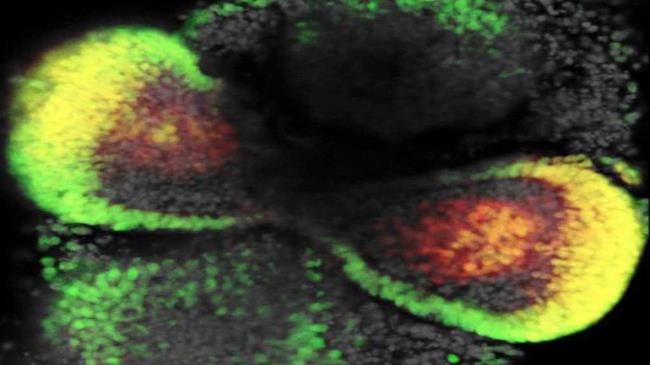

“El objetivo no es sólo hacerlo de la forma más cercana a una retina real, sino también posiblemente aprovechar la flexibilidad del sistema para crear maneras más diversas de estudiar el tejido de la retina”, ha explicado el autor del estudio, Mike Carl, a la revista Stem Cell Reports.

Según expertos del Centro Alemán de Enfermedades Neurodegenerativas (DZNE por su sigla en inglés), su versión de "mini-retinas", detallada en la edición digital del jueves de la mencionada revista, ofrece nuevas perspectivas sobre el crecimiento de la retina, el daño que puede recibir y los métodos para su reparación.

El objetivo no es sólo hacerlo de la forma más cercana a una retina real, sino también posiblemente aprovechar la flexibilidad del sistema para crear maneras más diversas de estudiar el tejido de la retina”, explicó el autor del estudio, Mike Carl.

Además, permitirá comprender con mayor agudeza la conformación del ojo humano; así como todo el desarrollo de la vista.

Los avances le han permitido a las autores del estudio mayor posibilidad y no descartan la posibilidad de crear nuevas retinas con vasos sanguíneos; lo que le permitiría entender la estructura celular del ojo y su funcionamiento.